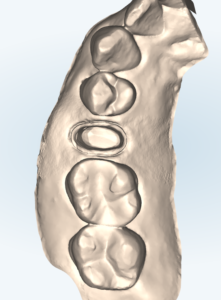

右上小臼歯のジルコニアクラウン

| 治療内容 | 右上の歯肉に腫れを認め、原因は被せ物が装着されている歯の内部の細菌感染であった。根管治療を行い、経過良好だったので、再び被せ物を作ることになった。材料は金属、プラスチック、セラミックのいずれかを選択できるが、健康的で審美的な材料を希望され、セラミックによる治療を選択された。噛む力が強いことが予想されたので、強度の高いジルコニアで被せ物を作る方針となった。 根管治療後にデジタル印象(型取り)を行い、ジルコニアクラウンを装着した。 |